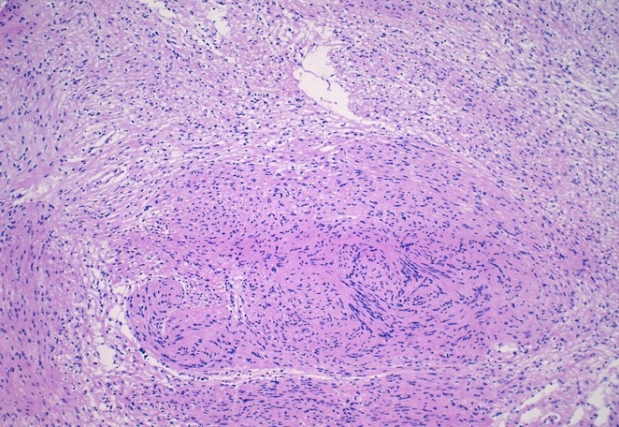

- Microscopically, breast schwannomas are well-circumscribed or encapsulated and can have prominent nodularity (Fig. 3A). Classic schwannomas have a bland spindle cell proliferation with various degrees of anisonucleosis, and wavy, elongated nuclei with tapering ends. These are arranged in parallel rows (nuclear palisading), also known as Verocay bodies (Fig. 3B). There is an abrupt transition between hypercellular (Antoni A) and hypocellular areas (Antoni B) (Fig. 3C). Antoni B areas have loose and myxoid stroma (Fig. 4A). Other key features to schwannomas include numerous small to medium sized vessels with prominent hyalinization and thrombi inside the lumen (Fig. 4B) and may also contain areas of hemorrhage or hemosiderin deposition [3,19].

Fig. 3.Excision of breast schwannoma with nodularity (A), Verocay bodies (B), and Antoni A and B regions (C).